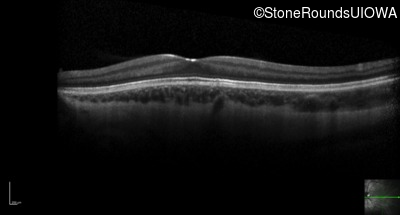

Optical Coherence Tomography - Right - 20/160 +1

Exemplar / OCT Stack

OCT Stack